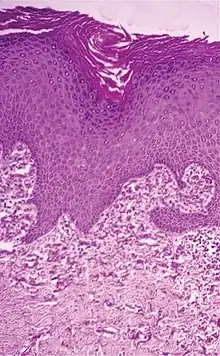

Histopathology of perforating calcific elastosis: Clumping of short elastic fibers in the dermis.[2]

Perforating calcific elastosis is an acquired, localized cutaneous disorder, most frequently found in obese, multiparous, middle-aged women, characterized by lax, well-circumscribed, reticulated or cobble-stoned plaques occurring in the periumbilical region with keratotic surface papules.[3]